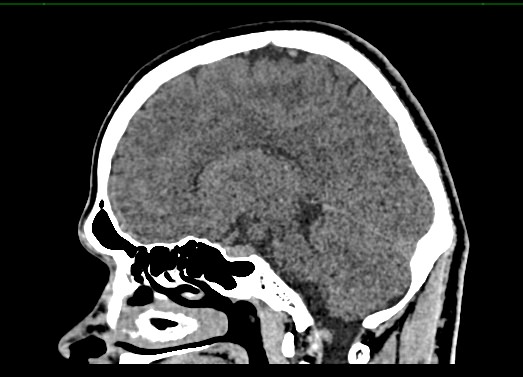

Методика построена на использовании проникающей способности рентгеновских лучей, которые в различной степени поглощаются органами и тканями (степень поглощения зависит от их плотности), благодаря чему можно получить подробные изображения внутренних органов. Во время исследования трубка томографа вращается вокруг пациента и производит снимки поперечного сечения, что позволяет детально визуализировать кости черепа и все структуры головного мозга.

Наши медицинские центры оснащены новейшими мультиспиральными компьютерными томографами экспертного уровня TOSHIBA AQUILION в различных модификациях. Аппараты снабжены увеличенным количеством сверхчувствительных детекторов, что позволяет при сканировании выполнять от 64 до 128 срезов поперечного сечения с минимальной толщиной среза от 0,5 мм. В результате получаются изображения исследуемой зоны в мельчайших подробностях, которые затем с помощью инновационных цифровых приложений преобразуются в трехмерные пространственные модели головного мозга для более точной диагностики.

Нативное сканирование подходит для диагностики дистрофических изменений головного мозга, определение острого нарушения мозгового кровообращения, как ишемического, так и геморрагического характера, а также отслеживание последствий подобных состояний при прохождении реабилитации.

Для улучшения видимости внутричерепных структур применяется методика внутривенного болюсного контрастирования. Во время проведения КТ пациенту в вену вводится йодсодержащее контрастное вещество. Контраст с током крови попадает в патологически измененные участки ткани и очаги, что на снимках придает им яркие отличительные признаки по сравнению с окружающими здоровыми тканями. Контрастирование, в первую очередь, помогает в диагностике опухолевых процессов на ранних стадиях, когда лечение может дать наилучший эффект.